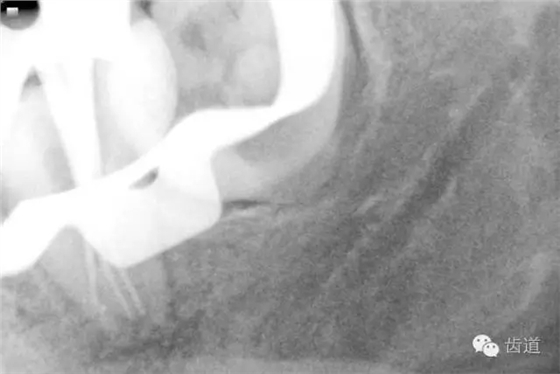

4. 術(shù)后根充X線片